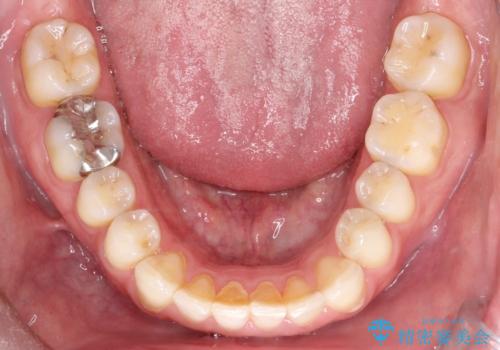

【インビザライン】前歯の隙間を閉じたい

- 前歯の隙間を主訴に来院されました。

マウスピース矯正にて、隙間を綺麗に閉じることができ満足していただきました。

前歯の隙間を閉じる際は、前歯部の突き上げが懸念されるため、適切な治療計画が必要となります。